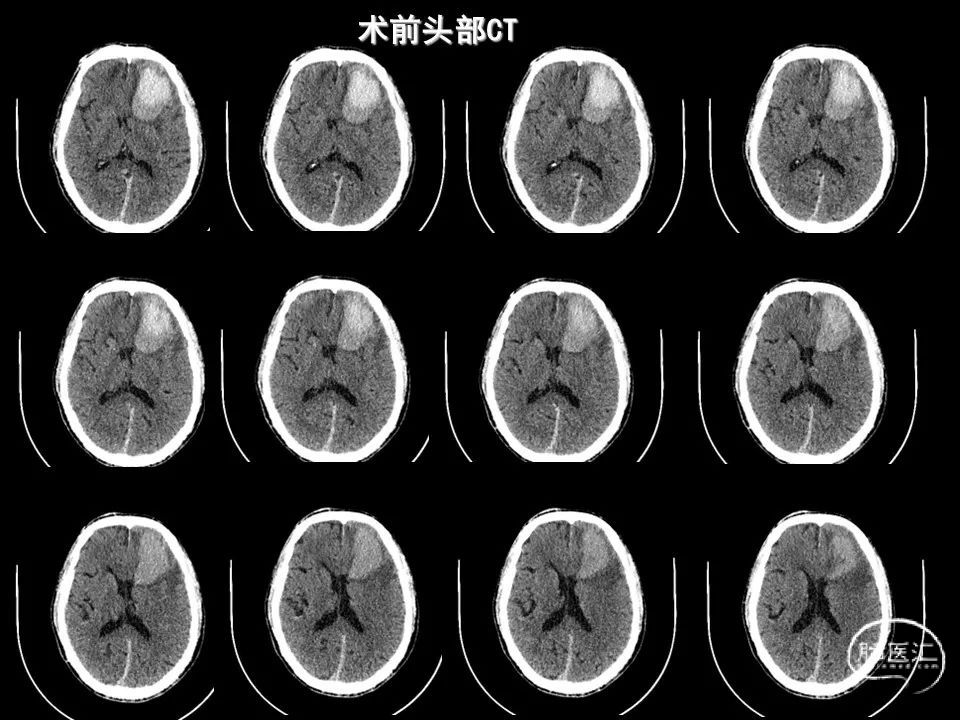

今天为大家分享的是《监测有道丨颅脑创伤-神经重症周刊》第338期,由海南省人民医院朱蔚林教授带来的:2例脑出血微创手术,欢迎阅读、分享。

主要从事神经内镜下垂体腺瘤、高血压脑出血手术,鞍区肿瘤,颅底肿瘤,脑膜瘤、听神经瘤、胶质瘤等显微外科手术,颅脑创伤,脑积水、蛛网膜囊肿、颅内感染等救治